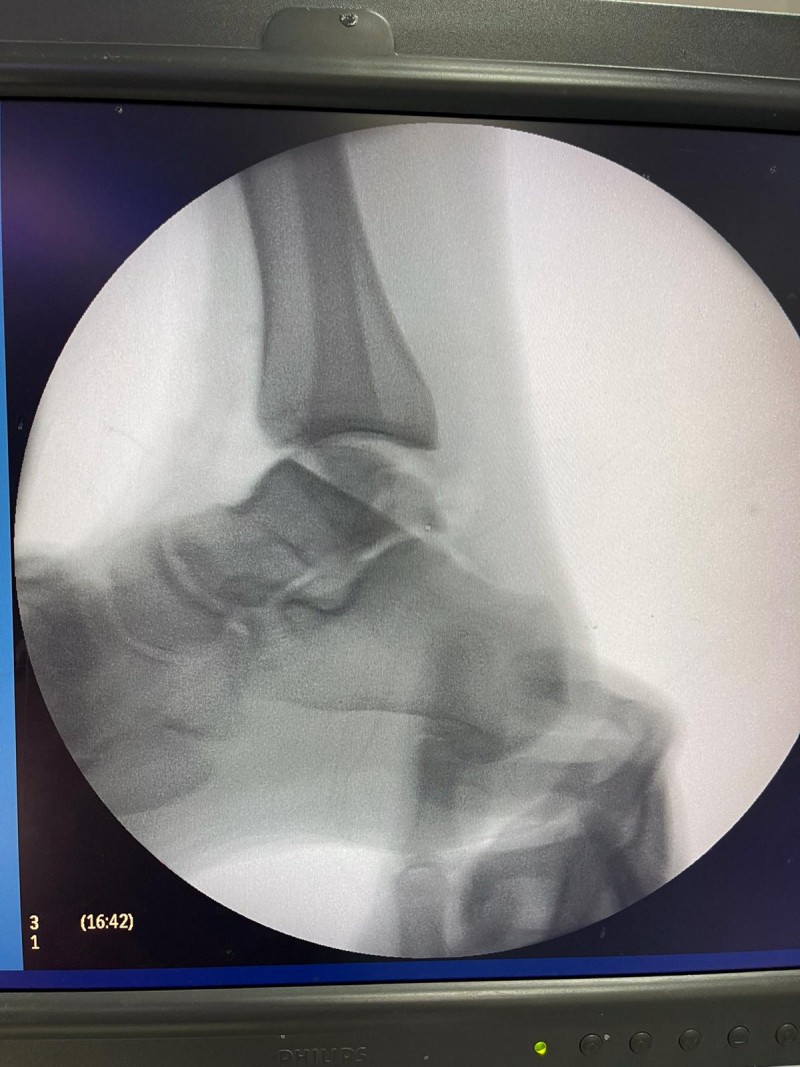

Hastanede yapılan, “Balıkesir’de ilk” nitelikli işlemlerin bir yenisi de Ortopedi ve Travmatoloji Anabilim Dalı Öğretim Üyesi Doç. Dr. Aziz Atik tarafından gerçekleştirildi. Gerçekleştirilen ameliyatla ilgili bilgiler veren Ortopedi ve Travmatoloji Anabilim Dalı Öğretim Üyesi Doç. Dr. Aziz Atik; “Lenf kanseri olan 21 yaşındaki hastamız lenf kanseri tedavisi görerek sağlığına kavuşmuş ancak ilerleyen zamanlarda aldığı tedavilerin yan etkisi olarak ayak bileği kemiğinde çürüme meydana gelmiş. Bize başvuran hastamızın eklem yüzeyi bozulmuş ve hastamız yürümekte zorlanıyor, topallıyordu. Büyük bir lezyonu olan hastamıza büyük lezyonlarda uygulanan en iyi tedavi yöntemi olan ve nadir olarak yapılan bir ameliyatla kadavra donörden kemik ve kıkırdak doku nakli gerçekleştirdik.” ifadelini kullandı. Ülkemizde kemik ve kıkırdak bankası olmadığının altını çizen Doç. Dr. Aziz Atik, yurt dışından bir donör bulmak için çalışmalar yaptıklarını ve yurtdışından kemik bulunduğunda ivedi bir şekilde ameliyatı gerçekleştirdiklerini söyledi. Ameliyatın son derece başarılı geçtiğini belirten Doç. Dr. Aziz Atik, güzel bir eklem düzeyi elde ettiklerini ve ameliyatla genç bir insanın topallamadan, ağrısız yürümesini hedeflendiklerini dile getirdi.